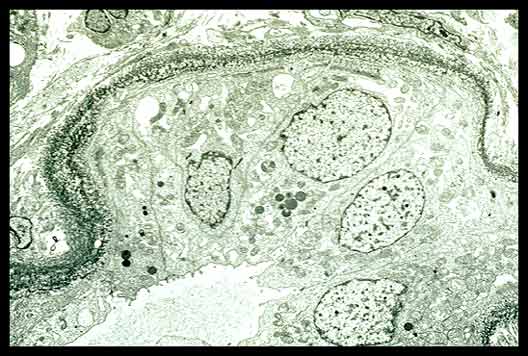

Amyloid fibrils by electron microscopy

Ultrastructurally, you see the classic fibrils that we are so used to seeing. In fact, before this whole issue of fibrillary glomerulopathy or immunotactoid glomerulopathy came into existence, I don't have any doubt that there were cases of so-called Congo red negative amyloidosis that may in fact have had ITG or fibrillary GN, if you will, because they were basing it on the ultrastructural features rather than on the fact that it was Congo red negative.

The ultrastructural features are they have these randomly oriented fibrils which have a diameter of about 9 or 10 nm. What is interesting is we always talk about these as fibrils or fibrillary glomerulopathy... amyloid is referred to as a beta fibrilosis. But if you look at these high-powered electron micrographs that Dr. Schwartz did, you can see that even the classic beta fibrilosis can have a microtubular-like appearance. I think it is fairly easy for those up front to see that these are microtubules, if you will. I guess the difference between a microfibril and a microtubule may be the magnification.